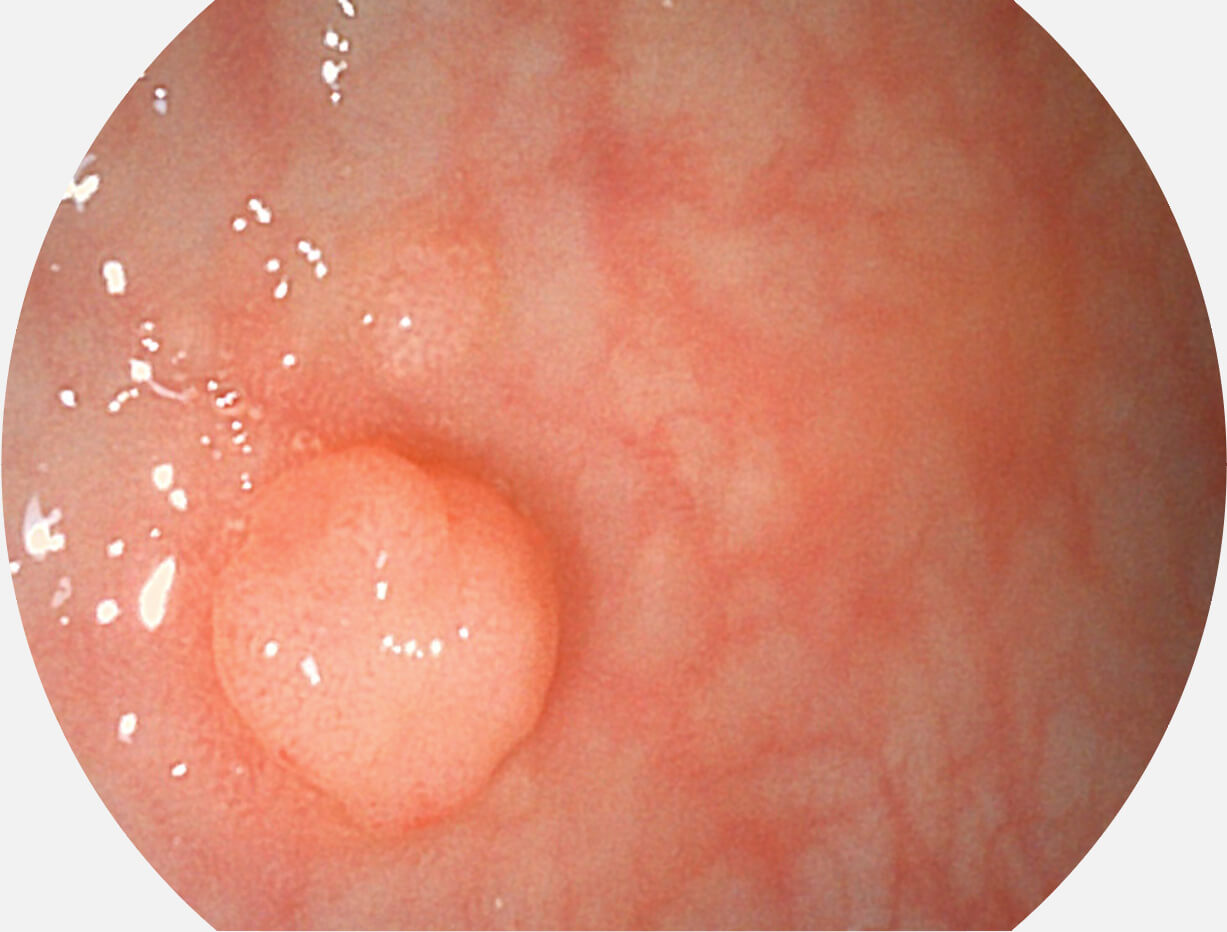

强调浅层黏膜结构的同时,保证照明亮度和提升浅层微血管与中层血管颜色对比度,病变边界更清晰。

• 白光图像 VIST图像